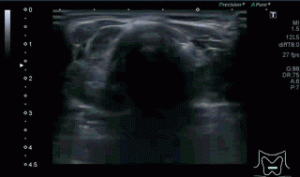

Era un nódulo hiperecogénico en el contexto de la tiroiditis en el estudio de una ecografía tiroidea.

Te enseño las imágenes, típicas de una exploración tiroidea de protocolo con semiología de tiroiditis.

De la imagen 1 a 7 el protocolo habitual, el estudio particular del nódulo con medidas y aplicación del doppler demuestra el aspecto típico del Caballero Blanco.

El Caballero blanco, recibe el nombre debido a su semiología hiperecogénica, homogénea y solitaria circunscrito en la patología referida con anterioridad, puede aparecer en esta patología de forma benigna o degenerar en otro tipo de patología a formas malignas como el linfoma tiroideo.